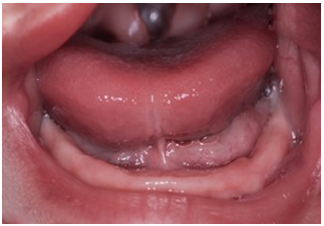

It has a unilateral hard and soft palate fissure, with cleft lip (right side) Figure 1, Figure 2, Figure 3, Figure 4, Figure 5.